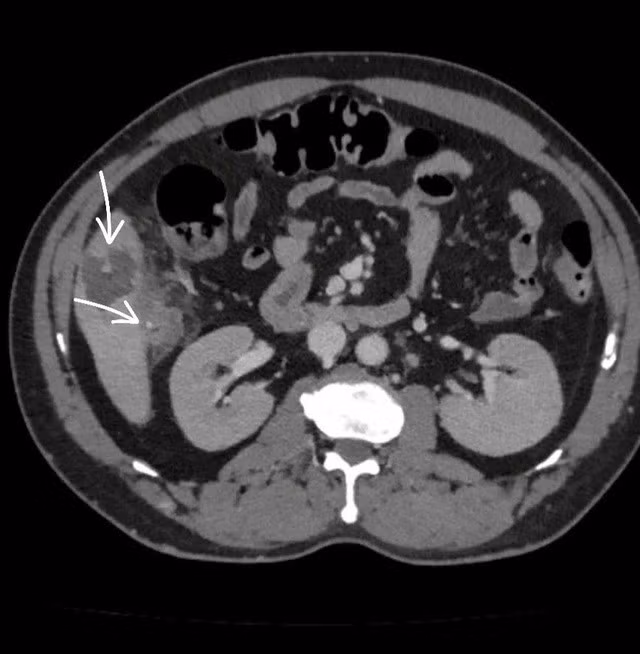

Kết quả chẩn đoán hình ảnh (CT scan) cho thấy một mảnh xương nhỏ xuyên qua thành đại tràng tại góc gan, găm vào nhu mô gan hạ phân thùy V, tạo ổ áp xe kích thước 56x36mm, kèm viêm dày thành đại tràng vùng góc gan. Đây là nguyên nhân chính gây ra ổ nhiễm trùng nguy hiểm. Bệnh nhân nhanh chóng được các bác sĩ phẫu thuật nội soi, lấy dị vật và xử lý ổ áp xe thành công. Sau phẫu thuật, bệnh nhân đáp ứng với điều trị, tình trạng dần ổn định và được chuyển sang Khoa Ngoại Tiêu hóa để tiếp tục điều trị.

Bệnh nhân bị áp xe gan do bị mảnh xương nhỏ đâm phải. Ảnh: BVCC/Nguồn SKĐS.